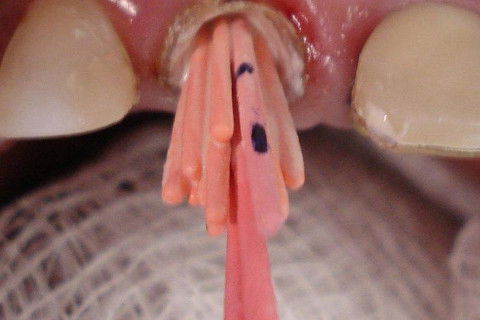

Aquecimento prévio do cone de guta-percha

Modelagem do terço apical

Paciente apresentou-se com elemento 11 contendo  retentor intra-radicular insatisfatório sobre tratamento endodôntico na mesma condição. Ao exame radiográfico pôde ser diagnosticada lesão periapical. Foi proposta e executada a remoção da coroa metalocerâmica e núcleo metálico fundido seguido de retratamento endodôntico cumprindo-se os princípios da terapia desde a cirurgia de acesso à obturação. Para tanto, optou-se pela técnica de moldagem prévia do cone de guta-percha empregando calor como uma variação da técnica de condensação lateral. pela dificuldade de travamento que o conduto apresentou por sua amplitude, além da preocupação pelo vedamento do terço apical.

Ao final, obteve-se sucesso endodôntico por meio de um selamento hermético, um travamento ideal utilizando a moldagem apical em um conduto amplos impedindo infiltração apical e permitindo uma visão tridimensional dos canais radiculares. A técnica é de simples execução, não necessitando de instrumental específico, porém requer habilidade clínica e conhecimento.